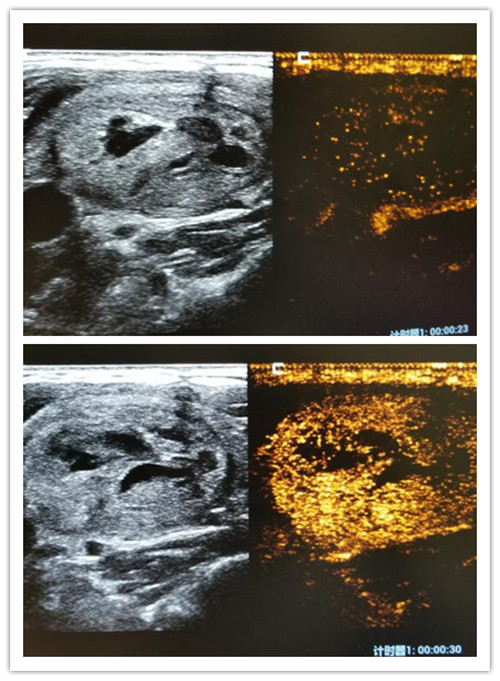

2、妊娠子宫的诊断、胎儿系统筛查及胎儿四维成像。早、中、晚期正常妊娠中胎儿生长、发育情况及其羊水、脐带、胎盘的监测。异常的妊娠有流产、异位妊娠(宫外孕)、胎儿生长发育迟缓、胎儿畸形(无脑畸形、脑积水、脊椎裂、消化道或泌尿系畸形等)、前置胎盘、胎盘出血、羊水量异常、脐带绕颈、滋养叶疾病(葡萄胎、恶性葡萄胎、绒毛膜癌等)。

高端四维彩超机GE-炫光E8